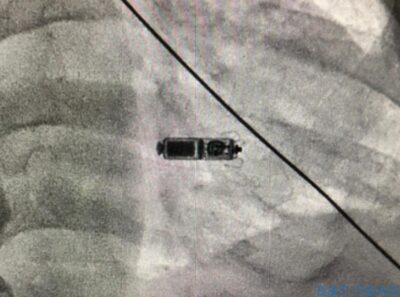

أكدت صحة جدة أن فريق طبي متكامل متخصص في كهربائية القلب التداخلية بمركز القلب التخصصي بمجمع الملك عبدالله الطبي في جدة, نجح في إجراء أول عملية زراعة منظم لضربات القلب لاسلكي لمريض عن طريق القسطرة القلبية التداخلية من خلال الوريد الفخذي دون الحاجة إلى فتح الجلد بالكامل ووضع أسلاك داخل القلب.

وبينت أن جهاز منظم ضربات القلب اللاسلكي يُساعد المرضى الذين لديهم تباطؤ شديد في نبضات القلب أو قصور كامل في كهرباء القلب على ممارسة حياة طبيعية وتجنّب أعراض الإغماء المتكرر.